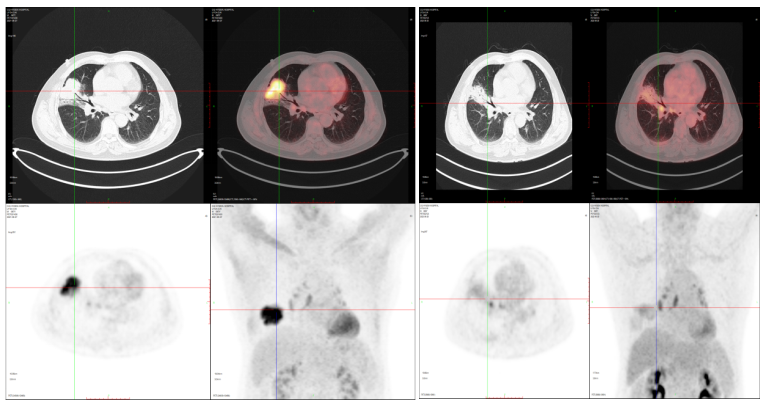

肺癌治疗后2021-9-27 2022-6-20